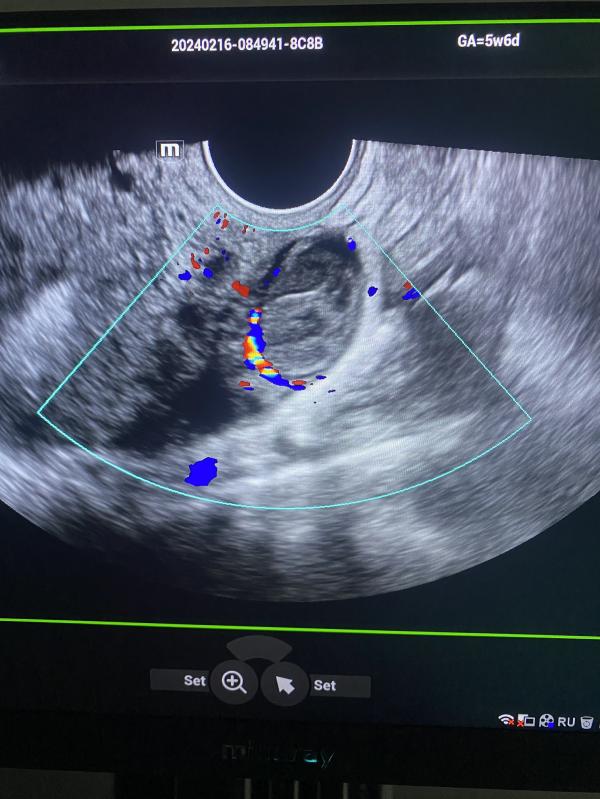

post image 2